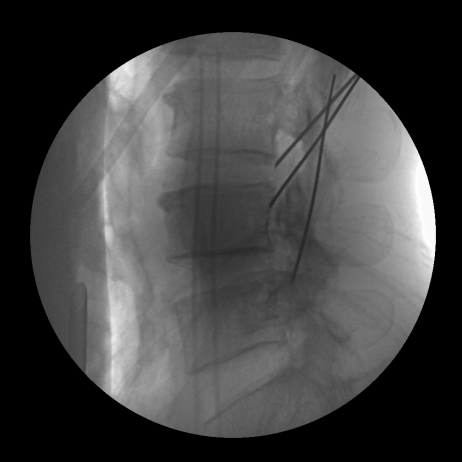

Reduced Radiation Dose

Fewer correction exposures mean significantly lower cumulative radiation for both healthcare professionals and patients.

Enhanced Surgical Precision

A-Beam® technology delivers superior accuracy, greatly reducing the likelihood of revision surgeries.